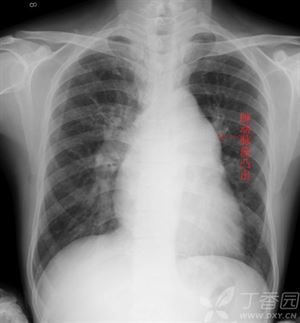

病情分析:你好!根据你说的症状吸烟40年,近一年来咳嗽咳痰,白色泡沫痰,活动后轻微气喘有可能是慢性气管炎的症状。指导意见:靴形心并不是一种疾病,而是心脏的一种形态改变

靴形心

普大型心、梨形心、靴形心的片子究竟怎么看啊